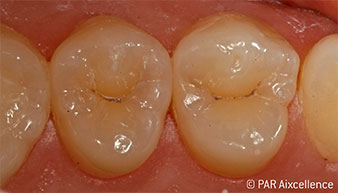

Рис. 9. Законченная долговременная реставрация